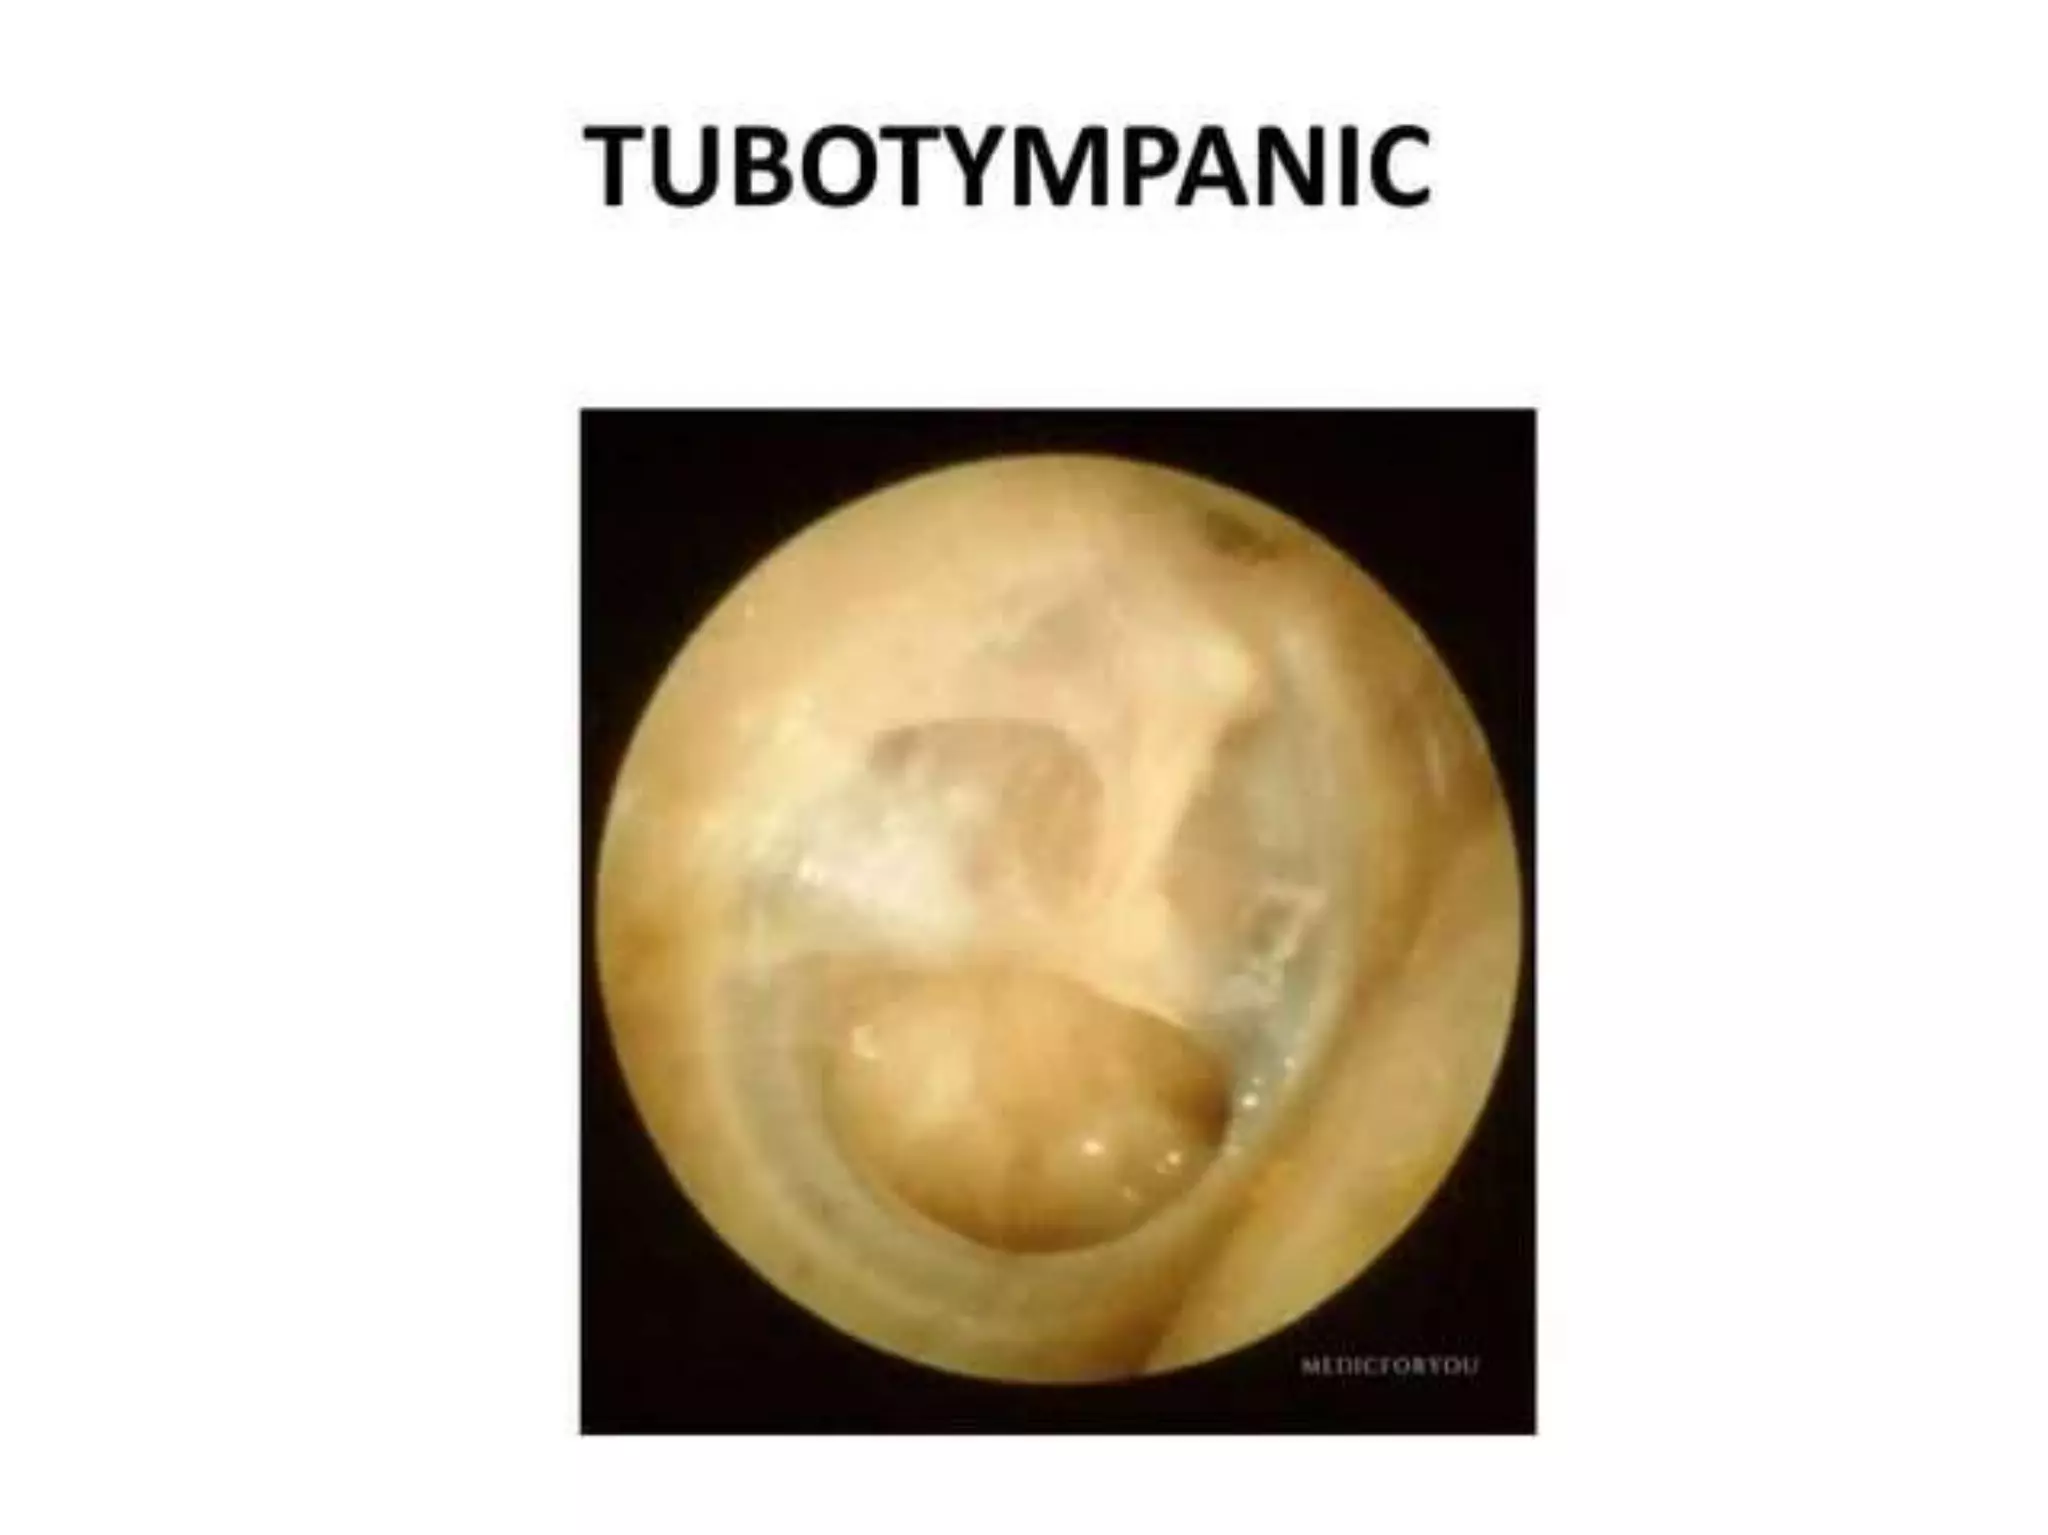

Chronic otitis media is a chronic inflammation of the middle ear and mastoid cavity that presents with recurrent ear discharge through a perforated eardrum. It has several subtypes depending on the state of the eardrum perforation and epithelium. It can be caused by prior acute otitis media, genetics, environment, eustachian tube issues, gastroesophageal reflux disease, craniofacial abnormalities, or immune deficiency.